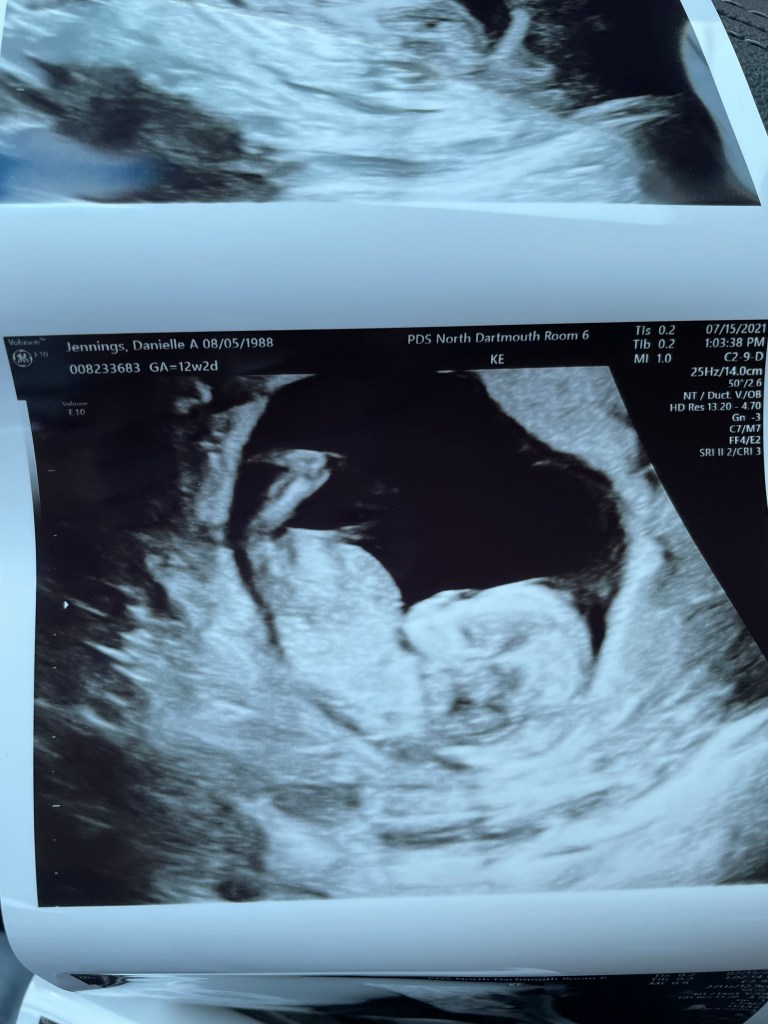

7/15/2021- NT Scan 12w2d. I know I will probably say this about every scan but oh my this one was amazing. We got to watch baby for 30 minutes on a big screen, the sono tech said the baby was moving so much that it was difficult to take any measurements. Today we got to see little limbs moving all over the place and even the babies brain. Everything looked good and we got some really nice pictures.